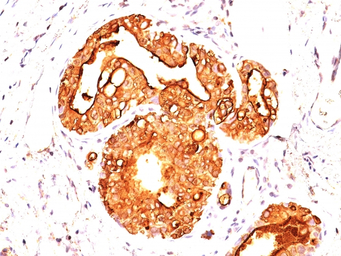

IHC-P analysis of human ovarian carcinoma tissue using GTX34852 MUC1 antibody [MUC1/955].

IHC-P analysis of human breast carcinoma tissue using GTX34852 MUC1 antibody [MUC1/955].